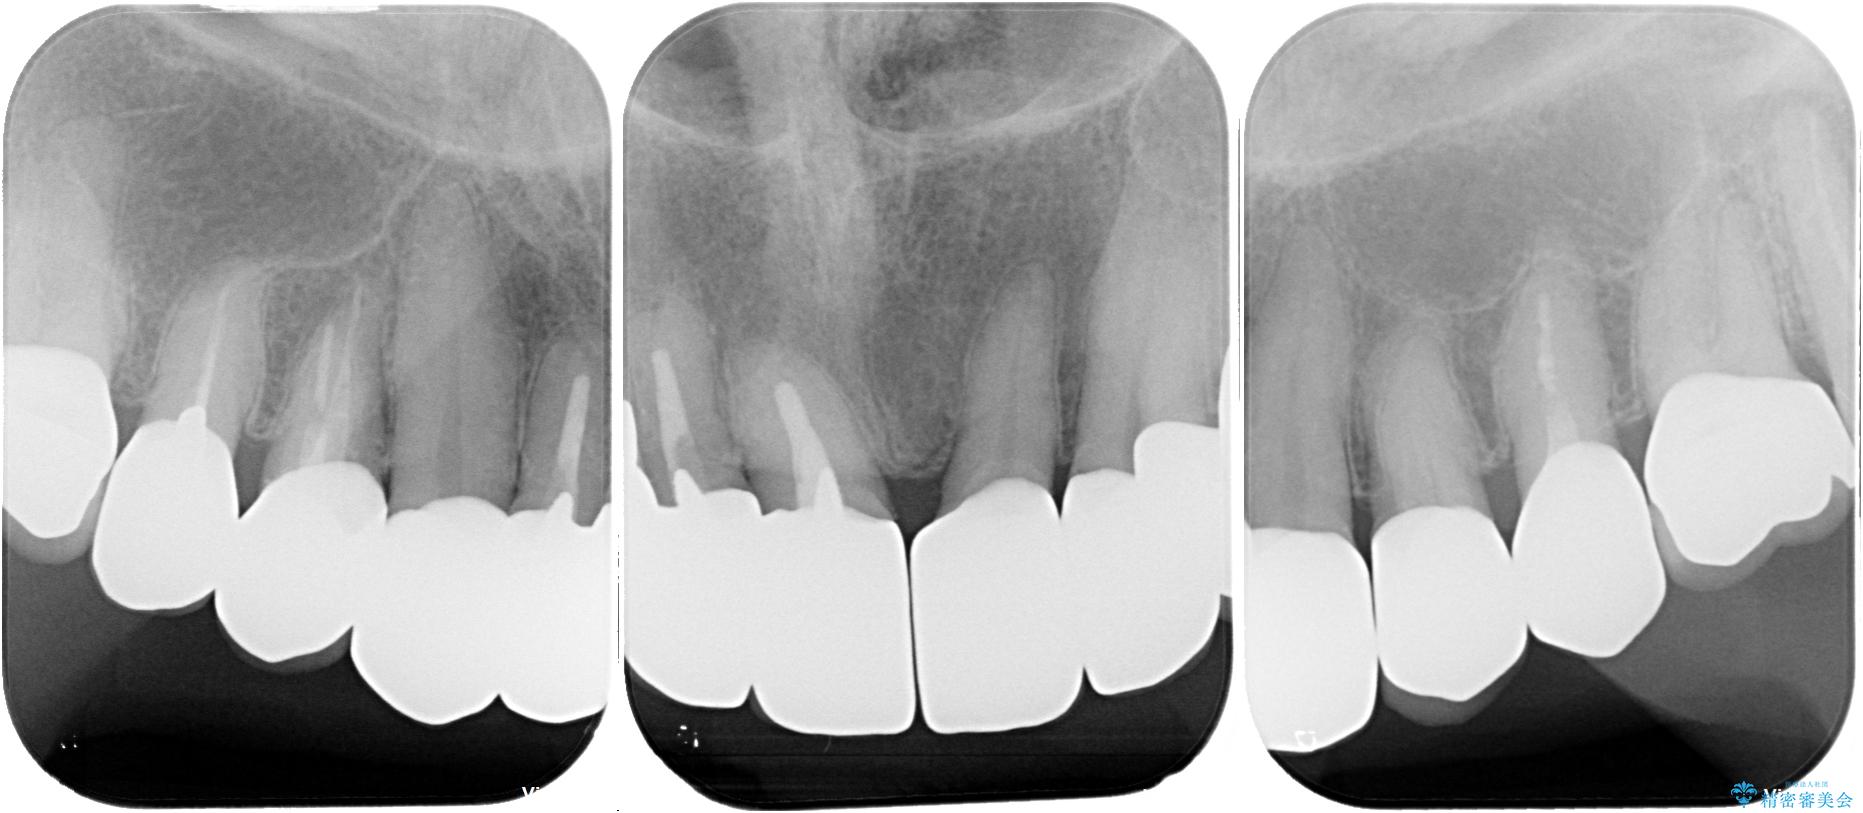

- 前歯のセラミックが欠けたり色調が不揃いであったりすることを気にして来院された患者様です。

20年以上前から、むし歯になったり詰め物が欠けたりする度に部分的に処置を行ってきたそうですが、この際統一感のある前歯にしたいとのことで、上顎前歯9本をオールセラミッククラウンによる補綴治療を行うこととしました。